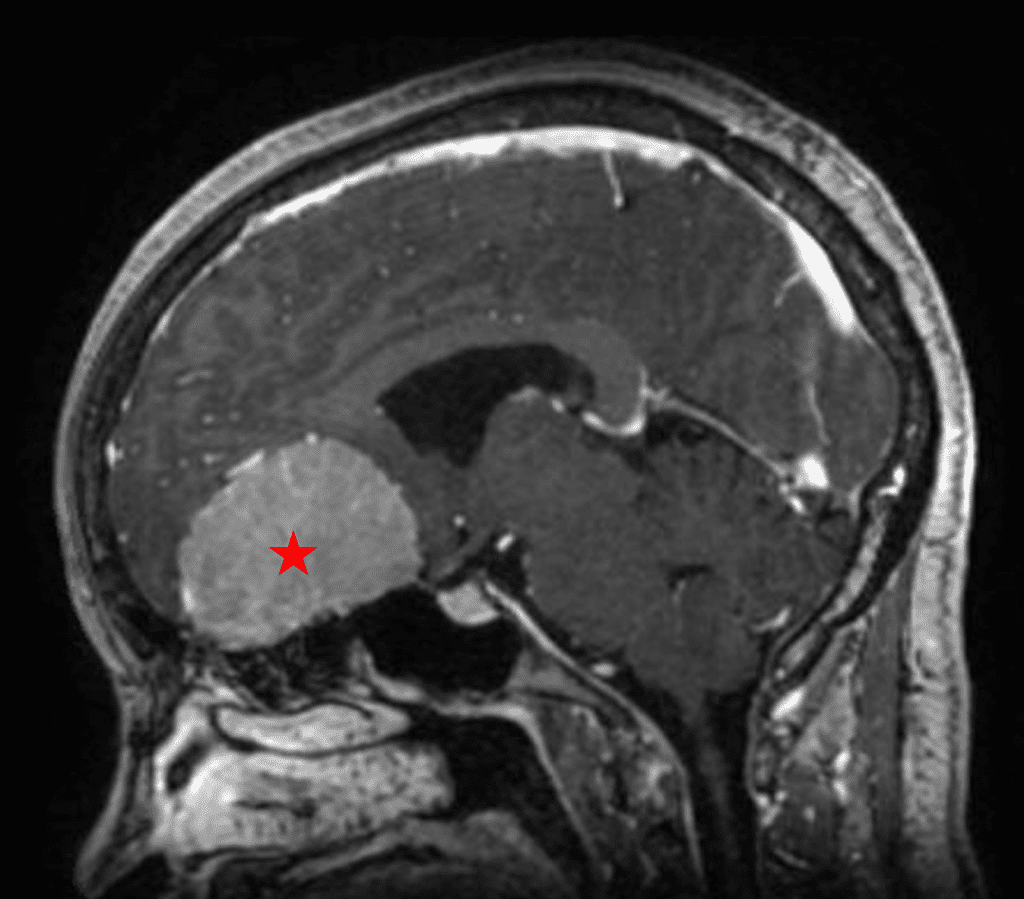

She was started on high-dose steroid and antiseizure prophylactic medicine. Surgical intervention was offered for mass effect, symptomatic relief, neurologic preservation, and histopathologic diagnosis. Dr. Gaudin performed a bifrontal craniotomy with complete resection of neoplasm through an interhemispheric and subfrontal approach. Postoperative imaging demonstrated a gross total resection without residual tumor and resolution of mass effect (Figure 1b and 2b). Intraoperative pathology was consistent with meningioma, WHO grade 1. She recovered very well, and was discharged home on postoperative day 3. On her follow-up outpatient visit, her preoperative symptoms had fully resolved, and her olfactory sense was maintained.

Figure 2a – Preoperative MRI demonstrating an extra-axial lesion with surrounding vasogenic edema and mass effect on the frontal lobes.